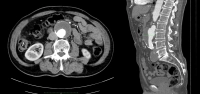

Filmbeispiel:

- infrarenales AAA, Durchmesser 54,2 mm

- Aneurysma der A. iliaca communis rechts, Durchmesser 41,1 mm